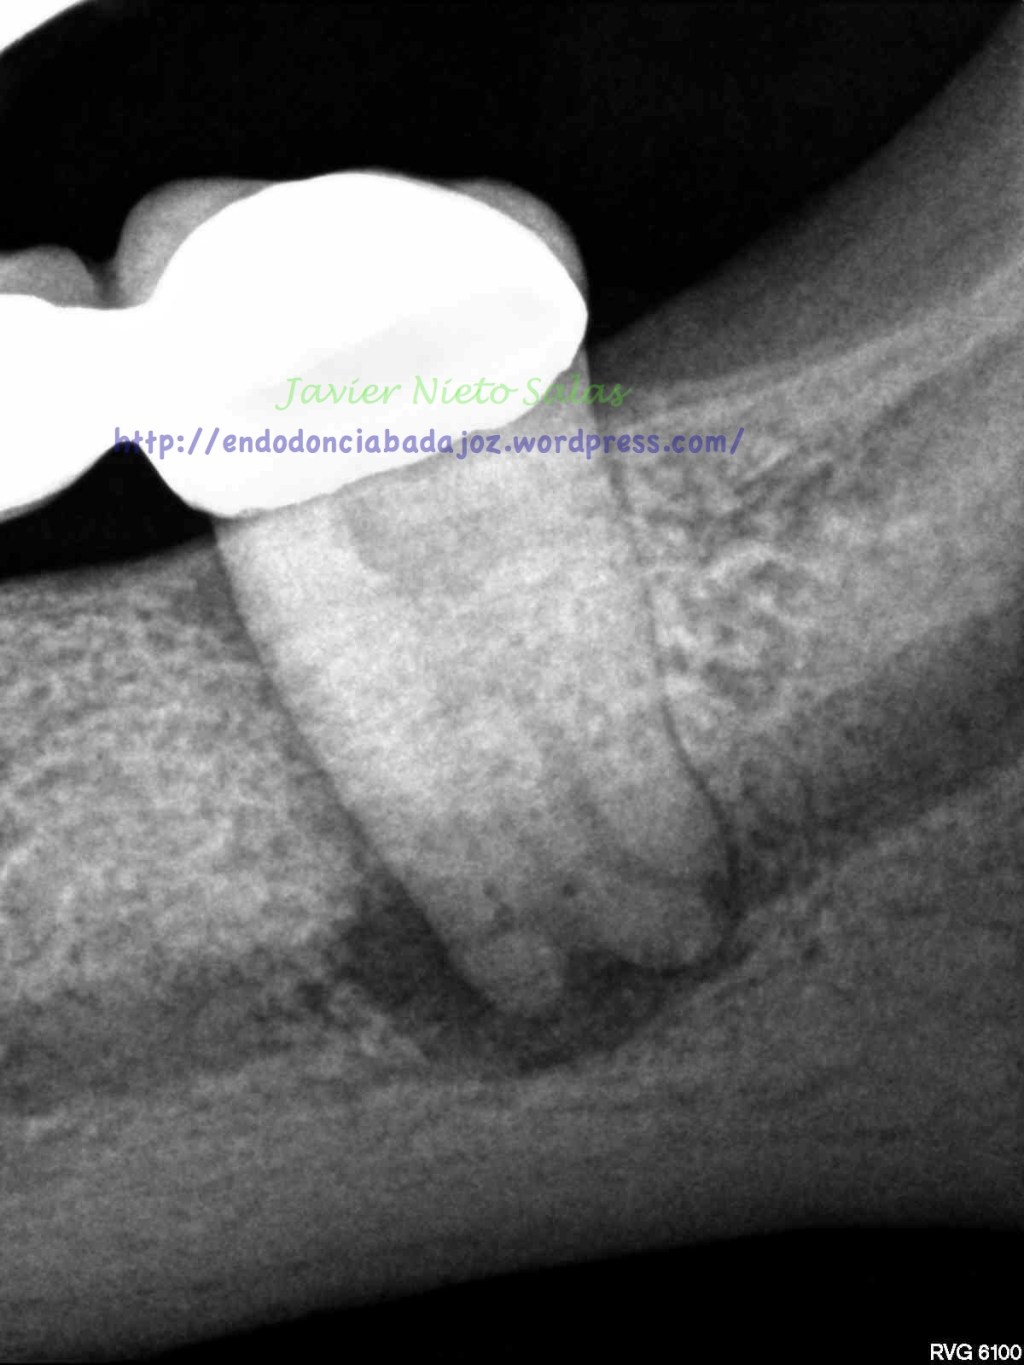

Pero el caso de hoy, no lo cuelgo por su dificultad, lo hago por varios motivos; el primero será el diagnóstico del caso, sólo radiograficamente, en este caso falta información, se puede sospecha de fractura vertical, por varios puntos, se trata de un segundo molar inferior, con un puente desde hace varios años, por la forma de la imagen de la lesión y el sondaje puntual. Pero como es sabido, el problema que tiene una «fractura vertical» es que todos esos signos coinciden con que puede tratarse de un «periodontitis apical crónica», como es el caso.

Pero cual es mi sorpresa y mi tristeza al ver la revisión del caso a los 9 meses. Filtración coronal con gran destrucción de la pieza, muy mal pronóstico.